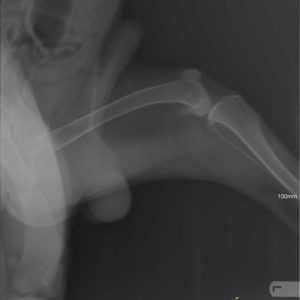

Vielen Dank an Alexander Englert, dass er möglich gemacht hat für Mex , seine Hüft- Dysplasie – Operation zu finanzieren. 🙂 Noch zweieinhalb Monate Rehabilitation und wir können eine neue Familie suchen für Mex! 🙂 Kategorie: NewsVon Csillag Alexandra2017-09-14 Share this post Share on FacebookShare on Facebook Share on XShare on X Autor: Csillag Alexandra http://www.ebarvahaz.hu KommentarnavigationZurückVorheriger Beitrag:Lola – Eine kleine wunder!NächstesNächster Beitrag:Vielen Dank Mirabella Hesz für die Spenden!Related postsTamara und ihre 7 kleinen Babys2026-01-13Hallo Mangó!2026-01-09Hallo unsere Lieben!2026-01-08Unsere neuesten Bewohner sind angekommen!2025-07-11Bözse <32025-04-10Überraschung2025-01-29